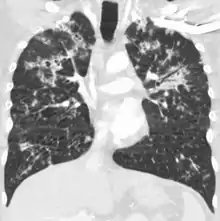

, , , , , ![]() Seu nome se refere a similaridade dos seus focos de infecção com grãos de milho espalhados pelo pulmão em 90% dos exames de raio-X. | |

Infecções tuberculosas generalizadas frequentemente causam alterações inespecíficas nos exames laboratoriais de rotina, podendo passar despercebidas em uma radiografia de tórax, sendo assim recomendado o exame de material obtido por punções, procedimentos cirúrgicos ou necropsias.[2]